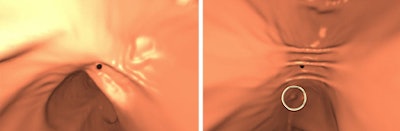

| In the prone-supine registration example above, which received a score of 4 for "near miss," the endoluminal field-of-view is centered on the registration prompt (black spot), and the polyp is evident but not directly marked (white circle). All images courtesy of Greg Slabaugh, PhD. |